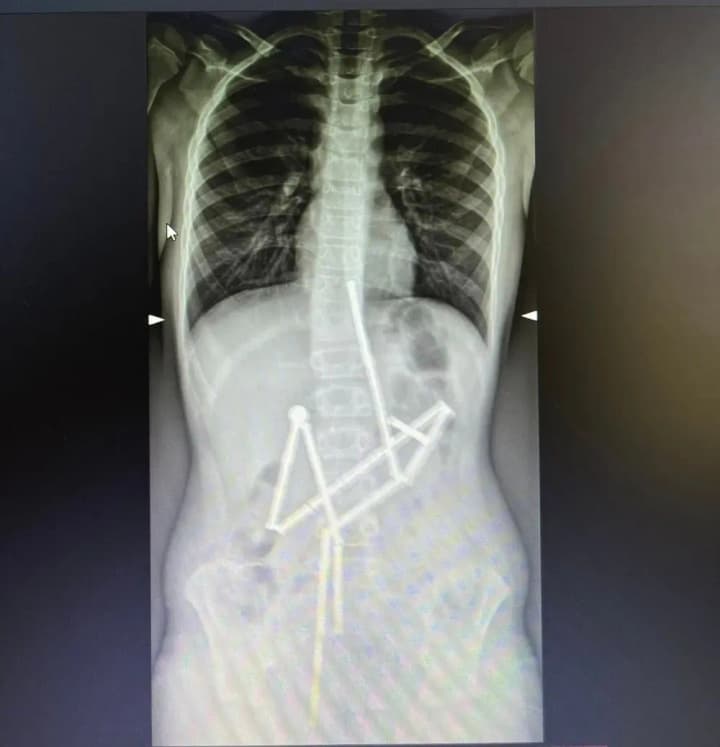

On the first X-ray, the specialists saw the presence of various foreign bodies in the digestive tract. 20 magnets were located in different parts of the gastrointestinal tract, but were connected to each other

In the end, most of the magnets (18 pieces) were removed one chain at a time by the doctors of the endoscopy department. However, one magnet remained and had to be removed by surgeons.

A laparotomy was performed and a thorough examination of the abdominal organs was carried out. During this, 5 perforation holes and the last element of the construction set were found in the child. All the holes were closed and the magnet was removed.